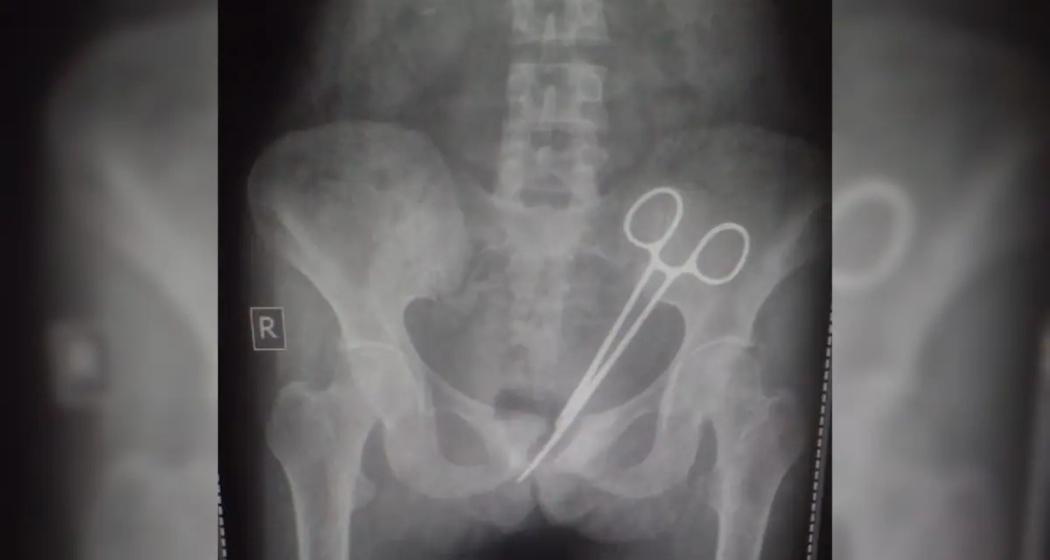

An X-ray reveals the surgical forceps left inside the patient’s abdomen.

In a shocking case of medical negligence at STNM Hospital in Sikkim, a patient underwent surgery on October 8, 2024, to remove surgical scissors that had been left inside her abdomen for over a decade.

On October 8, she went to the STNM hospital again and an X-ray revealed the surgical scissors in her abdomen.

"Even after the appendix operation, the woman had pain. Her family brought her to the STNM Hospital. In the X-ray, a surgical scissor was found in her abdomen. The doctors on Thursday operated to remove the scissor from the abdomen of the woman," he said.